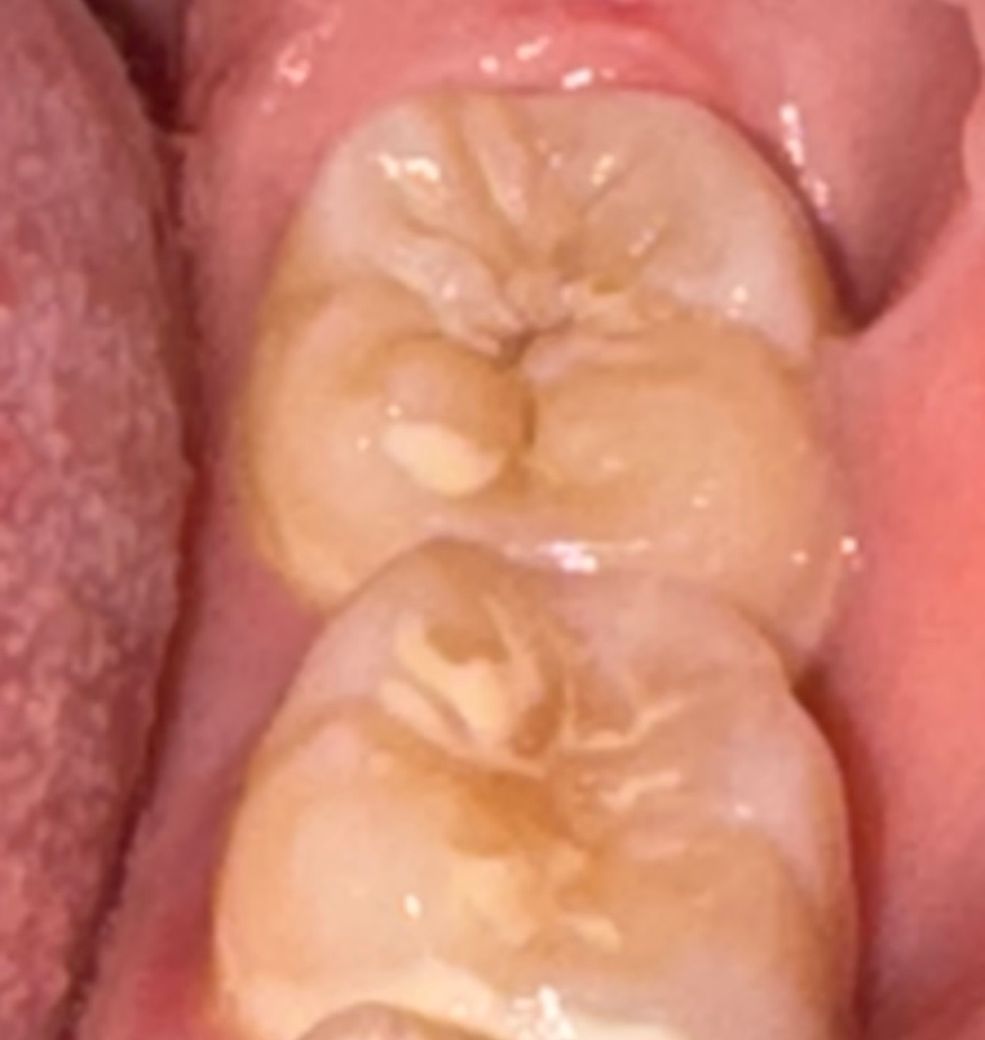

사진 속 치아 충치 많이 심한상태인가요?

맨 끝 치아에 충치가 있는 것 같기는 합니다. 겉에서 보기엔 얼마 안썩어보이는데 저런 양상이 안에서는

깊고 넓게 썩어들어가는 경우가 많아서 이미 진행중인거라면 사실 막을 방법은 없습니다. 치은염약도 효과가 없겠습니다.

정확한건 엑스레이를 찍어봐야 알겟지만, 육안상으로는 충치가 깊어 보이진 않아 보입니다.